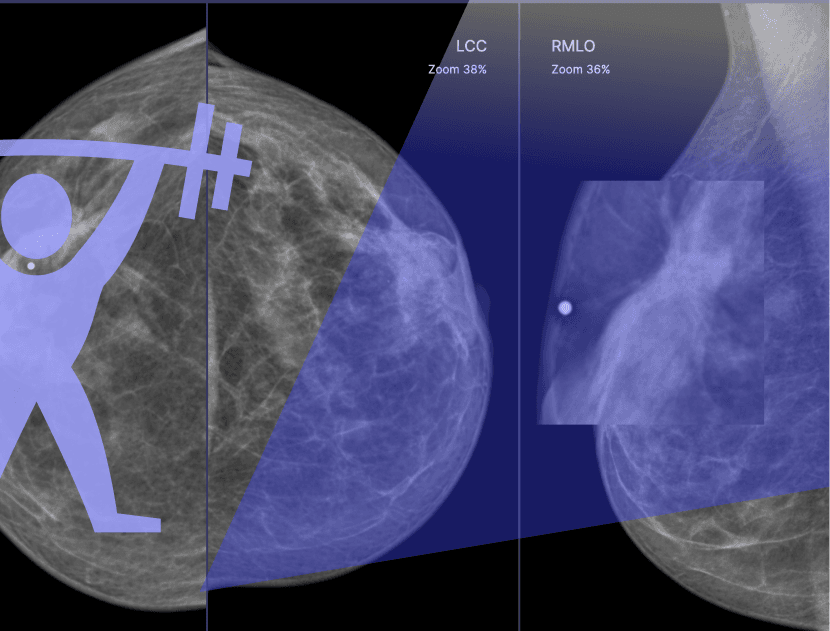

Тренажерный зал супермаммолога это регулярные еженедельные разборы маммографических кейсов с экспертом.

Каждый четверг для самостоятельного просмотра открывается очередной набор из 50 специально подобранных маммографических кейсов, а неделю спустя данные кейсы разбираются вместе с экспертом на онлайн-вебинаре.

Состав тренировок приближен к реальной жизни: большая часть кейсов — норма, но в небольшом числе маммограмм (2-7) спрятана патология или доброкачественные образования.